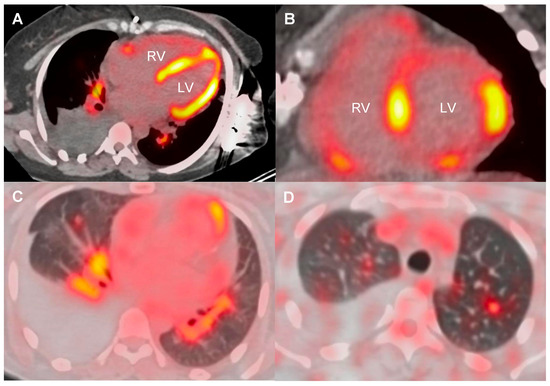

| 18F-FDG PET-CT | |||

| FDG uptake pattern | |||

| Cardiac alone | 4/22 (18.2%) | 0/10 (0.0%) | 3 (42.9%) |

| Cardiac and mediastino-hilar LN | 9/22 (40.9%) | 7/10 (70.0%) | 1 (14.3%) |

| Cardiac, lung, and mediastino-hilar LN | 6/22 (27.3%) | 3/10 (30.0%) | 1 (14.3%) |

| LV FDG uptake: No. of segments involved | 5.5 (2.0–8.0); n = 20 | 5.5 (2.5–6.8); n = 10 | 5.0 (2.2–7.8); n = 6 |

| RV FDG uptake | 7/22 (31.8%) | 5/10 (50.0%) | 0 (0.0%) |